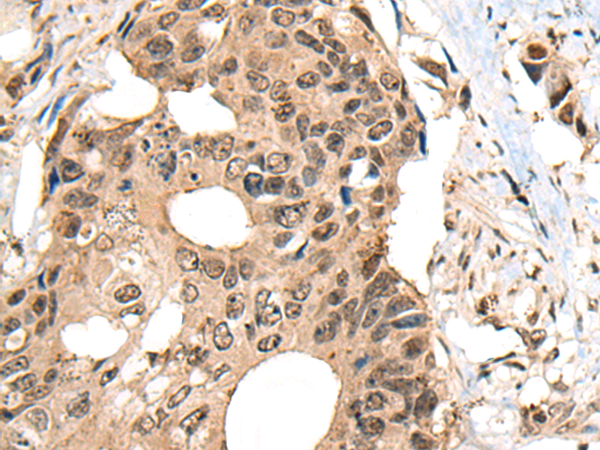

IHC positive control:

Human thyroid cancer and human colorectal cancer

IHC Recommend dilution:

30-150